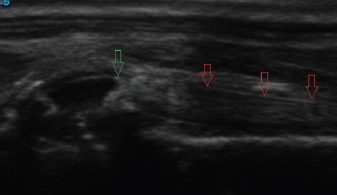

Fig. 3. Longitudinal ultrasound image of an intact biceps tendon (red arrows), supraglenoid tubercle (blue arrows), and proximal humerus (green arrows).

The dog was placed in lateral recumbency with the affected limb uppermost. Hair was clipped to expose the humeral tubercle and intertubercular groove. Using a 12 mHz linear probe, the biceps tendon was visualized longitudinally from the musculotendinous junction within the groove, proximally to the tendinous origin on the supraglenoid tubercle (Fig. 3). Any abnormalities and the approximate tendon size were noted. The biceps tendon was then positioned under tension by placing the shoulder in flexion with concurrent elbow extension, so that the forelimb lay roughly parallel to the topline. With the limb in this position, the appearance of the biceps tendon as it spanned the glenohumeral joint was noted, and images were saved to the ultrasound’s hard drive.